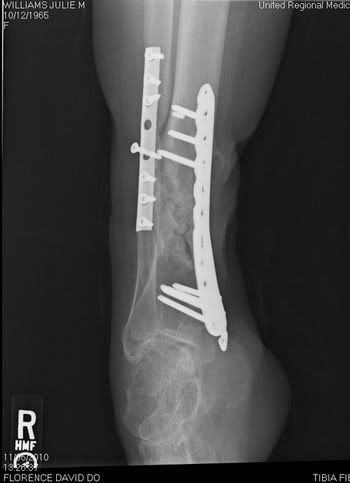

Most people don't understand why I am the way I am. I hope these x-rays give them a better idea of what I have to deal with every single day.

My right tibia (shin)